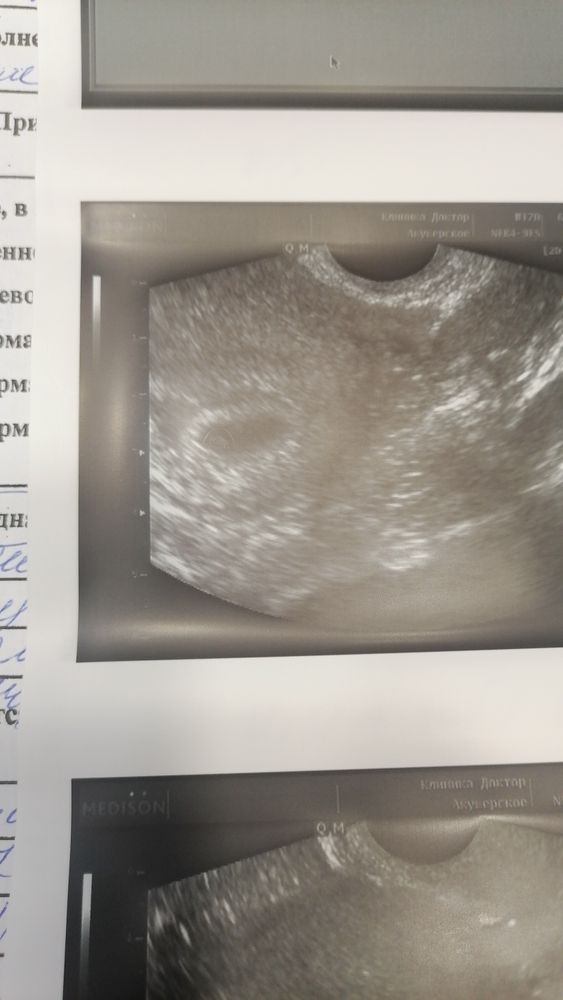

Повторное узи 10 дней задержки